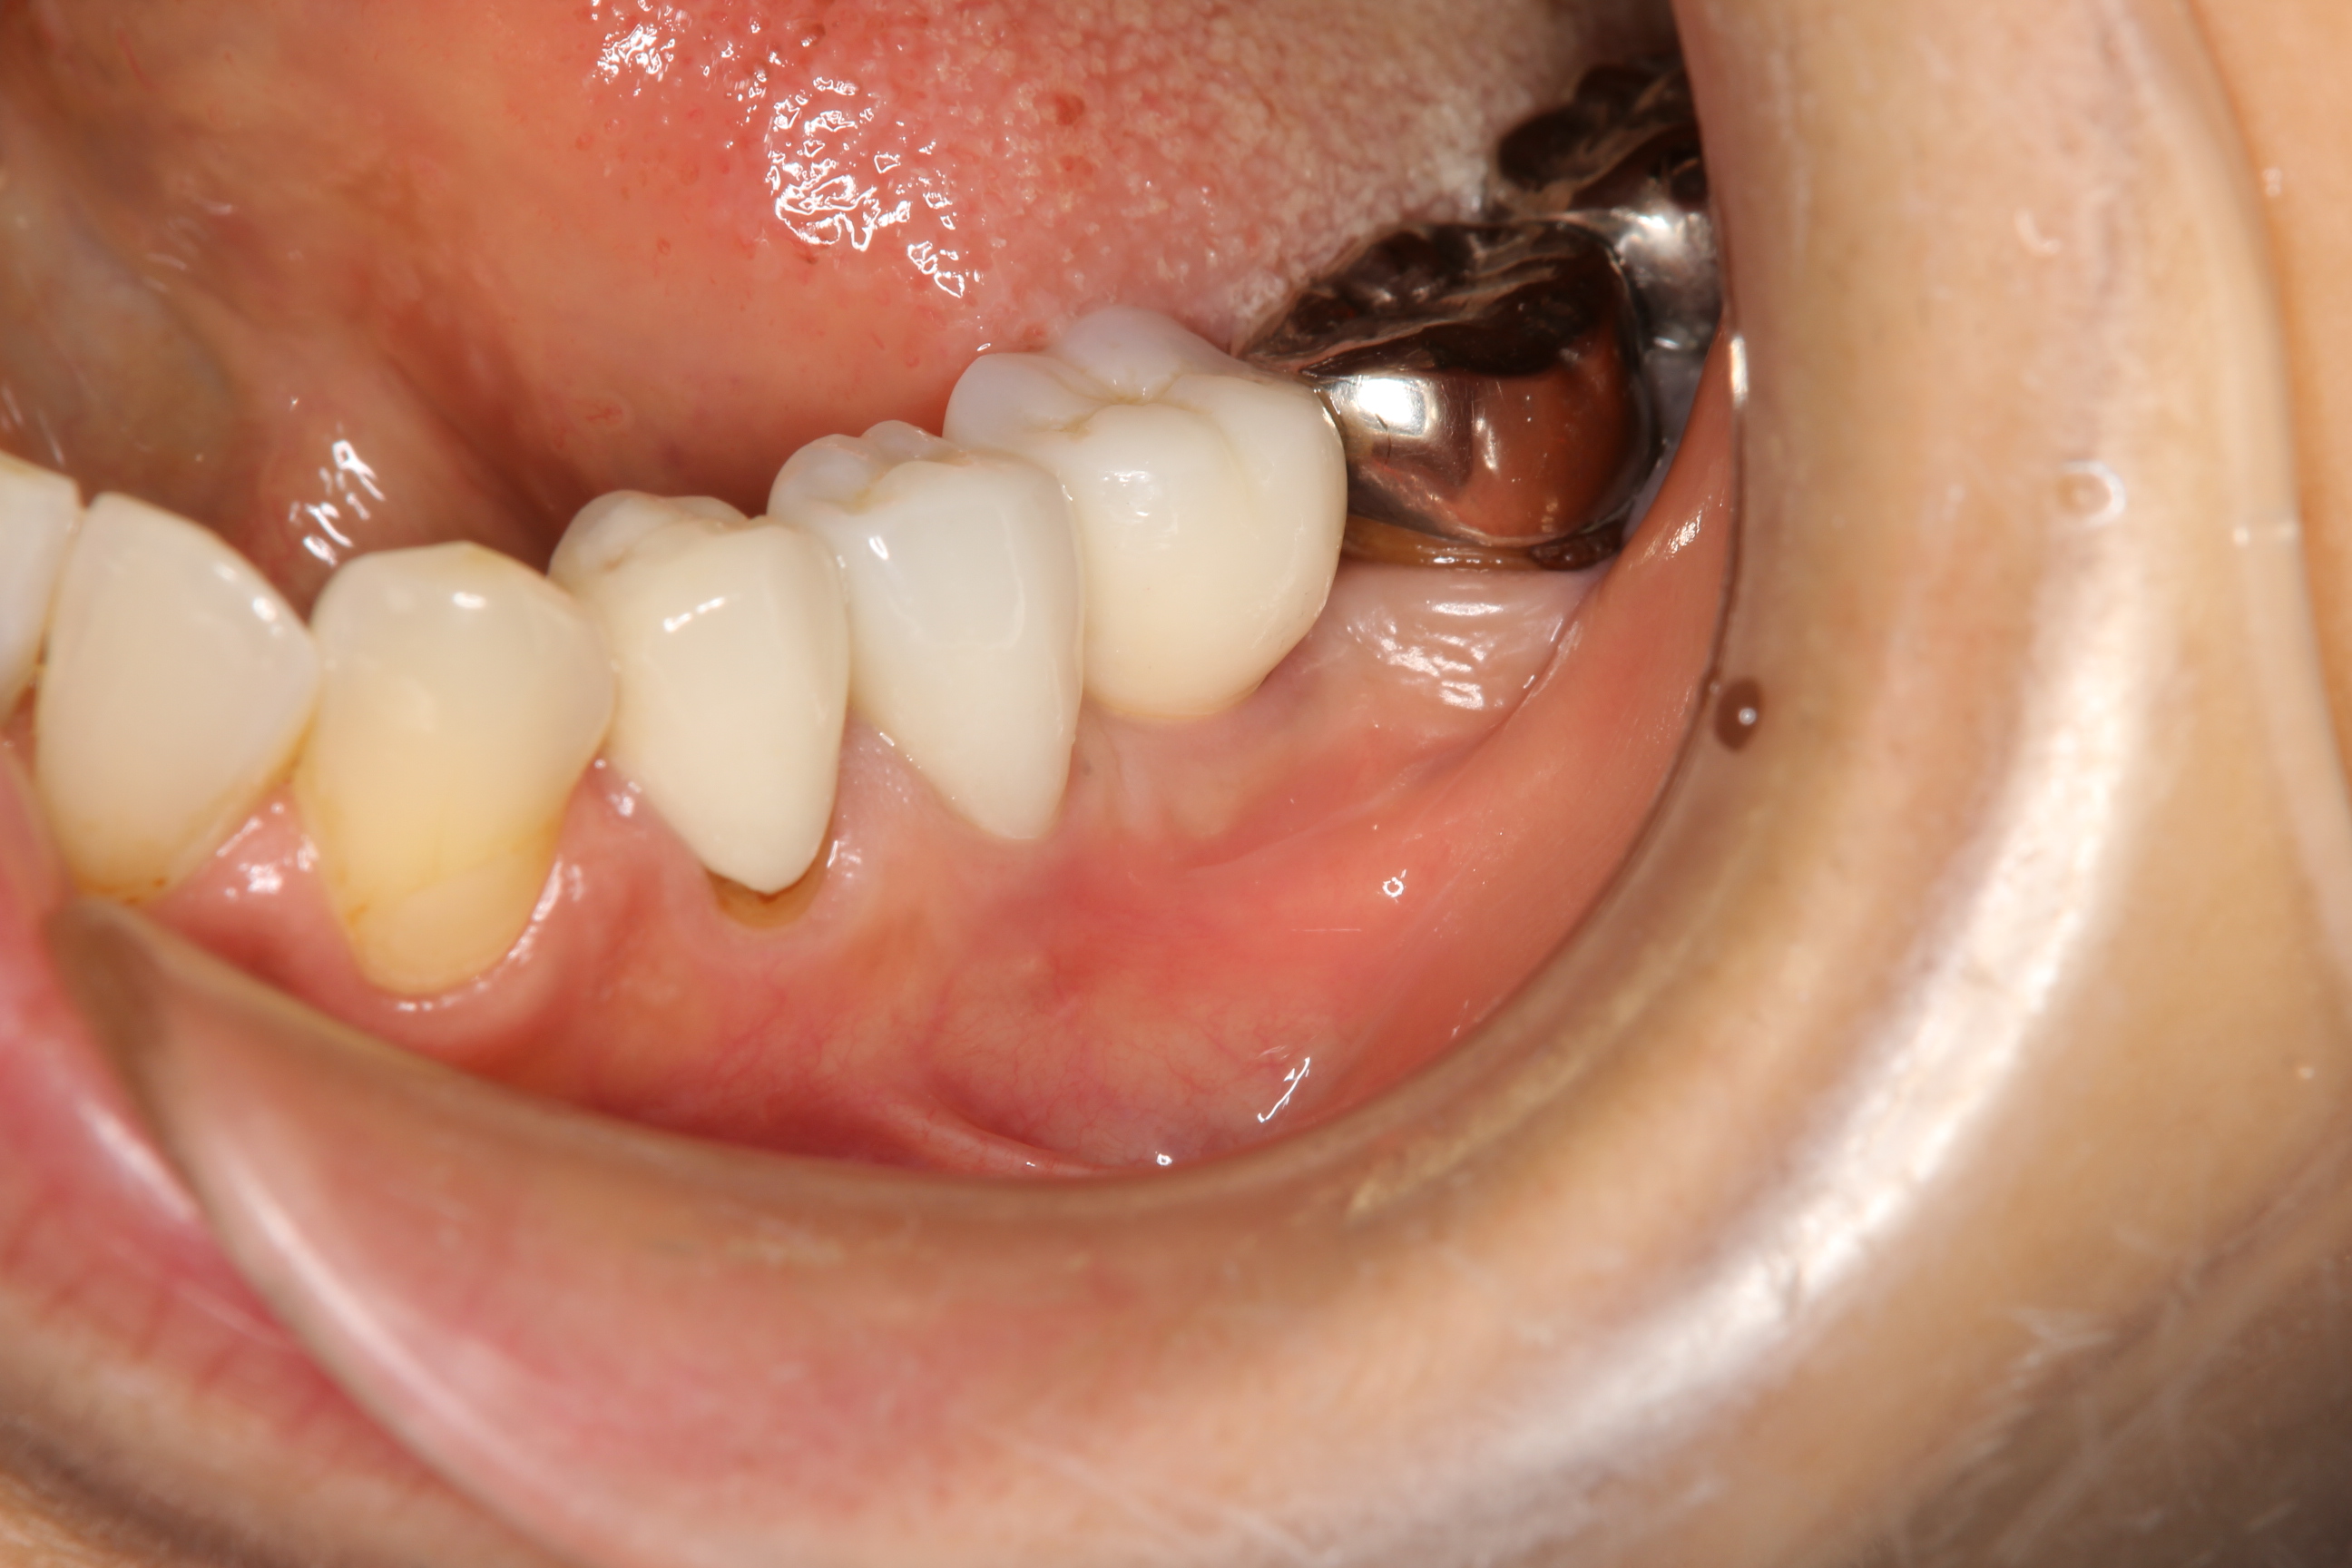

そして、クラウンを装着すると写真のようになります。

インプラント上部構造もクラウンも周囲と調和しており、患者さんにも満足していただきました。